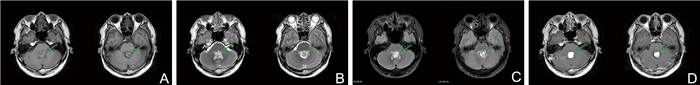

The clinical study of Bushen Huoxue Decoction combined with unilateral biportal endoscopy (UBE) in the treatment of lumbar spinal stenosis with kidney deficiency and blood stasis

E Yuan, HUANG Shengchang, RUI Lining

2025, 23(10): 1764-1767. doi: 10.16766/j.cnki.issn.1674-4152.004224

72 3

Abstract:

Objective  To evaluate the effects of Bushen Huoxue Decoction combined with unilateral biportal endoscopy (UBE) in patients with lumbar spinal stenosis (LSS) of kidney deficiency and blood stasis, focusing on recovery, inflammatory response, and postoperative complications, and to explore the therapeutic effect of integrated Chinese and Western medicine.  Methods  From June 2023 to April 2024, 120 patients with kidney deficiency and blood stasis type LSS were enrolled at Wujin Hospital of Traditional Chinese Medicine, Changzhou, and randomly divided into a treatment group (Bushen Huoxue Decoction + UBE) and a control group (UBE alone). The indicators such as visual analogue scale (VAS) score, Oswestry disability index (ODI) score, changes of serum interferon-γ (IFN-γ)/ interleukin-1α (IL-1α) were assessed.  Results  The treatment group demonstrated a higher overall response rate compared with the control group [86.67% (52/60) vs. 71.67% (43/60), χ2=4.093, P=0.043]. The VAS score in the treatment group was lower than that in the control group at 2 weeks and 1 month postoperatively (P < 0.05), while ODI score was lower at 1 and 6 months (P < 0.05). After treatment, serum IFN-γ and IL-1α levels in peripheral blood were significantly reduced in the treatment group compared with the control group (P < 0.05). The incidence of postoperative complications was also lower in the treatment group [6.67% (4/60) vs. 23.33% (14/60), χ2=6.536, P=0.011].  Conclusion  Bushen Huoxue Decoction combined with UBE can significantly improve the efficacy of kidney deficiency and blood stasis type LSS, reduce postoperative VAS and ODI scores, decrease serum IFN-γ and IL-1α levels, and reduce the risk of postoperative complications, supporting its value as an integrated therapeutic strategy.